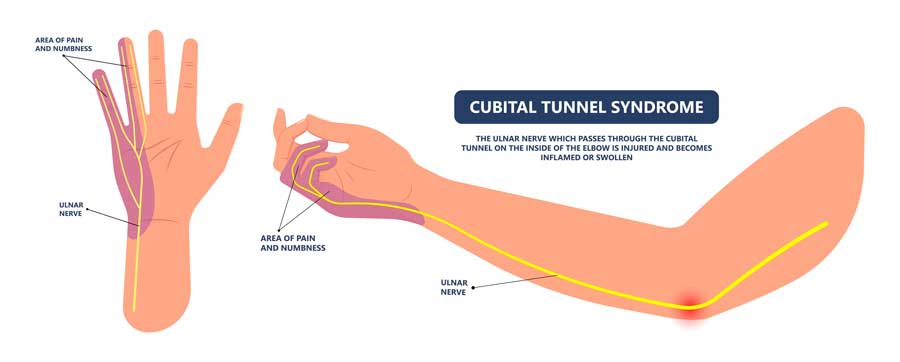

La compresión del nervio cubital en el codo ó síndrome del túnel cubital, es la compresión del nervio cubital alrededor del codo. Se trata de la segunda causa más frecuente de neuropatía periférica del miembro superior por atrapamiento, después del síndrome del túnel carpiano.

El nervio cubital en el codo tiene un trayecto superficial y está más influido por traumatismos directos, fuerzas de compresión y elongación.

El nervio cubital es uno de los tres principales nervios del brazo. Se origina en el plexo braquial y recorre el brazo hasta la mano.

En el codo, pasa por el túnel cubital, una región estrecha situada en el lado interno del codo, rodeado por hueso, lígamentos y tejido blando. Este nervio es responsable de la sensibilidad en el dedo meñique y la mitad del anular, así como del control de ciertos músculos intrínsecos de la mano que permiten movimientos finos.

El espacio limitado del túnel cubital lo hace susceptible a compresión o irritación, lo que conduce al desarrollo del síndrome del túnel cubital.

Los síntomas que produce la Compresión del Nervio Cubital pueden ser sensitivos y motores.

- Los síntomas sensitivos del síndrome cubital consisten en parestesias (hormigueos), disestesias (dolor) o falta de sensibilidad en el 4º y 5º dedos y zona cubital del dorso de la mano, irradiadas en ocasiones hasta el codo por la cara interna. Estos síntomas suelen aumentar con la flexión del codo y ser más acentuados por la noche.

- Los síntomas motores del síndrome cubital son falta de fuerza en la mano, atrofia de la musculatura intrínseca y mínima garra del 4º y 5º dedo (figura 2).